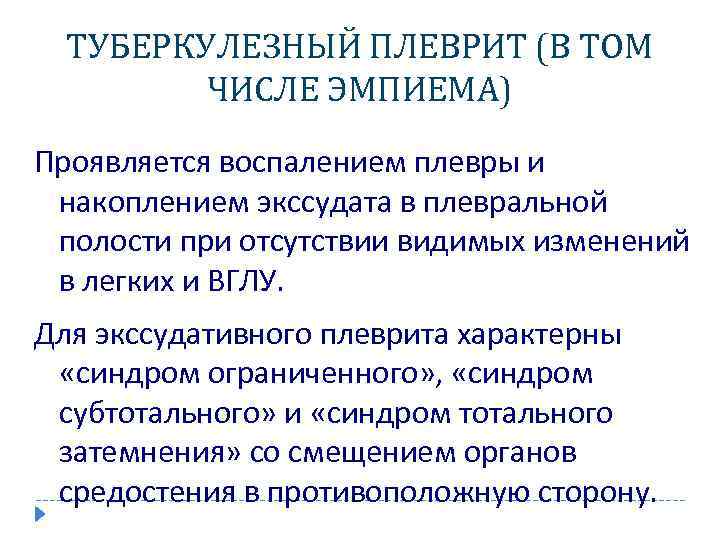

ТУБЕРКУЛЕЗНЫЙ ПЛЕВРИТ (В ТОМ ЧИСЛЕ ЭМПИЕМА) Проявляется воспалением плевры и накоплением экссудата в плевральной полости при отсутствии видимых изменений в легких и ВГЛУ. Для экссудативного плеврита характерны «синдром ограниченного» , «синдром субтотального» и «синдром тотального затемнения» со смещением органов средостения в противоположную сторону.

ТУБЕРКУЛЕЗНЫЙ ПЛЕВРИТ (В ТОМ ЧИСЛЕ ЭМПИЕМА) Проявляется воспалением плевры и накоплением экссудата в плевральной полости при отсутствии видимых изменений в легких и ВГЛУ. Для экссудативного плеврита характерны «синдром ограниченного» , «синдром субтотального» и «синдром тотального затемнения» со смещением органов средостения в противоположную сторону.